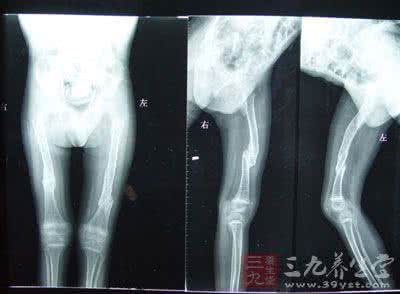

身高不到140厘米,手指长度只有3厘米,45岁的荆州妇女李畅(化名)得“怪病”40年没查出病因。直到因摔倒骨折才意外查出“怪病”竟是“先天性成骨不全”,一种发病率只有0.7/100000的罕见病。

昨天,记者在某医院骨科见到李畅,乍一看有点像“侏儒症”,双手的大小和七八岁左右的孩子差不多。她说她5岁就开始发育不良,个子定格在“138厘米”就不长了。因为家里穷,她一直没去查到底得了什么“怪病”。

李畅说,她这一跤是去年摔的,屁股着地,当时背部非常疼,小腿有种“被绳子捆住的感觉”,走路像踩棉花。到同济医院骨科就诊,才发现除胸椎骨折外,她的颈椎、胸椎及腰椎管还多处狭窄。经该院多次会诊,被确诊为“先天性成骨不全”,必须手术治疗。

成骨不全(osteogenesis imperfecta)是一种少见的先天性骨骼发育障碍性疾病,又称脆骨病或脆骨-蓝巩膜-耳聋综合征。其特征为骨质脆弱、蓝巩膜、耳聋、关节松弛,是一种由于间充质组织发育不全,胶原形成障碍而造成的先天性遗传性疼痛。其病变不仅限于骨骼,还常常累及其他结缔组织如眼、耳、皮肤、牙齿等。本病具有遗传性和家族性,但也有少数为单发病例。